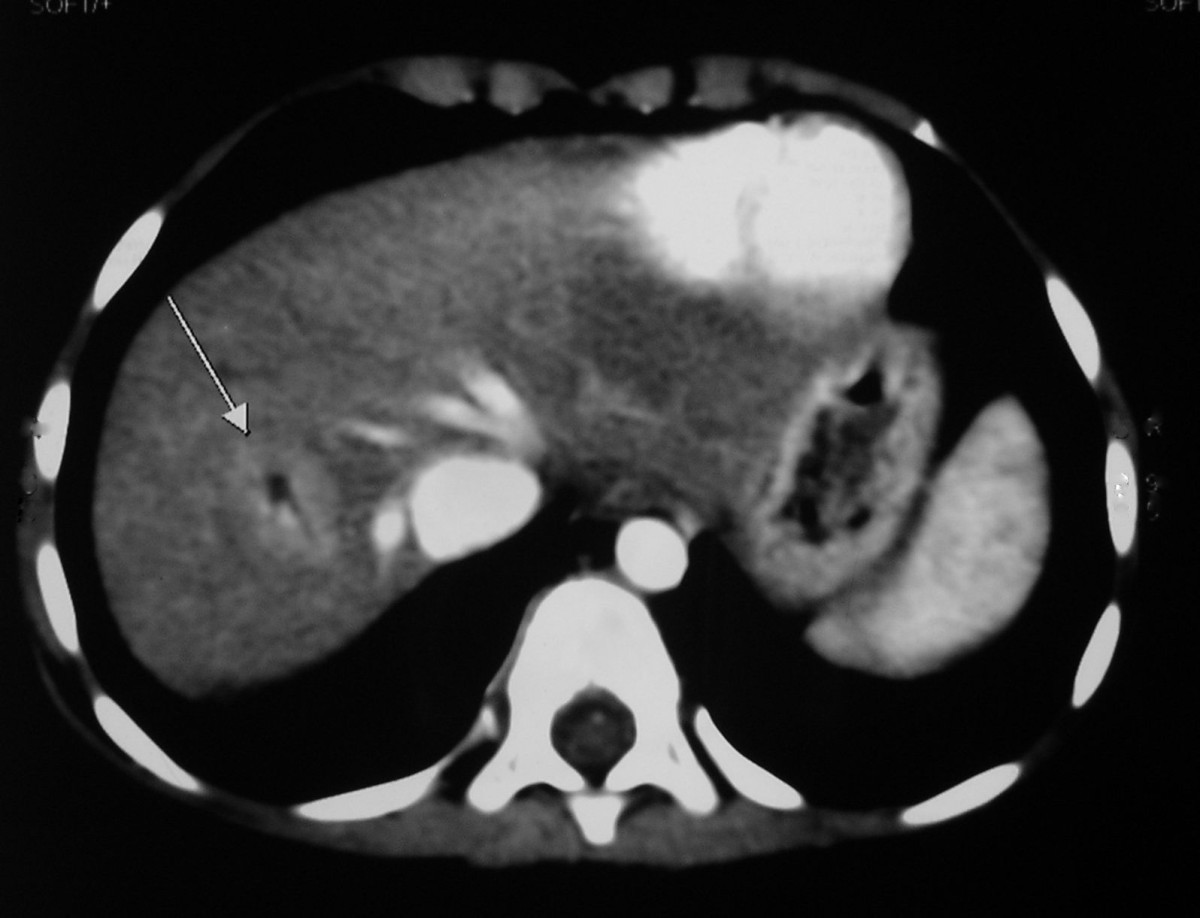

Cureus Congenital PortoAzygous Shunt Malformation Type II

Type 1B Abernathy malformation. (AD) Axial computed tomography images Abernethy Malformation Ct Web congenital extrahepatic portosystemic shunt (ceps), also known as abernethy malformation, is a rare condition. Web abernethy malformations are rare vascular anomalies of the splanchnic venous system. Web abernethy malformation is diagnosed via noninvasive cross‐sectional imaging such as transthoracic. Web abernethy malformation is a rare condition in which portomesenteric blood bypasses the liver and drains into the systemic vein. Web. Abernethy Malformation Ct.